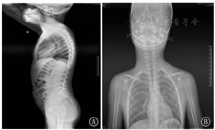

患儿,男,7岁5个月。患儿自幼右眼斜视,斜视角:角膜映光法:右眼偏斜角度为10°;2个月开始反复皮肤湿疹;1岁头面部反复米粒样红斑、丘疹、脓疱,瘙痒明显,部分破溃后出现糜烂、渗出,外院抗感染治疗症状可好转,但易反复;2岁因"细菌性肠穿孔"于外院行梅克尔憩室切除术;4岁5个月因"头面部反复红斑、脓疱3年余,加重3 d"至郑州大学第一附属医院皮肤科就诊。其他症状:眼距增宽,右眼眼球凸出,高腭弓。血常规示白细胞11.3×109/L、血红蛋白109 g/L、血小板342×109/L、中性粒细胞计数6.7×109/L、嗜酸性粒细胞计数0.77×109/L。免疫球蛋白补体测定示IgA 0.61 g/L、IgG 9.65 g/L、IgM 0.99 g/L、IgE 2.5×106 IU/L、C3 1.34 g/L、C4 0.269 g/L;淋巴细胞亚群检测示T淋巴细胞0.67、辅助性T淋巴细胞0.37、抑制性T淋巴细胞0.23、B淋巴细胞0.24、自然杀伤细胞(NK细胞)0.08、辅助/抑制淋巴细胞1.62。电解质、肝肾功、尿常规等均正常。胸部CT:双肺透亮度可,纹理清晰,两上肺见絮状稍高密度影。头颅磁共振成像(MRI):左侧额叶点状异常信号,考虑白质脱髓鞘,双侧颞角稍大,双侧脑室增宽。予抗感染治疗,症状好转,出院后症状反复,间断自行口服抗生素治疗。7岁反复出现颈部淋巴结冷脓肿,其他表现有脊柱侧弯、面部不对称、眼距增宽、高颚弓(图1);血常规:白细胞6.5×109/L、血红蛋白113 g/L、血小板317×109/L、中性粒细胞计数2.18×109/L、嗜酸性粒细胞计数0.68×109/L;免疫球蛋白补体测定:IgA 0.7 g/L、IgG 11.68 g/L、IgM 1.66 g/L、IgE 25.92×106 IU/L、C3 1.36 g/L、C4 0.11 g/L;脓肿穿刺行细菌培养提示金黄色葡萄球菌感染;彩超:左侧颈部混合型包块(58 mm×62 mm)。CT:左侧颈部间隙软组织占位并周围增大淋巴结,考虑炎性包块可能,双侧颈动脉鞘内增多小淋巴结。颈部脓肿病理:淋巴结反应性增生,局灶性化脓性炎;免疫组织化学:角蛋白单克隆抗体AE1/AE3(CK)(-)、CD3+CD20(灶+)、B淋巴细胞活化特异性蛋白(PAX-5) (灶+)、CD10(生发中心+)、CD21(淋巴滤泡树突细胞+)、CD30(散在+)、增殖细胞核抗原(Ki-67) (约40%+)、骨髓瘤相关基因MUM-1(+)。心电图:左心室高电压;脊柱立位、侧位片:脊柱以胸8椎体为中心轻度侧弯(图2)。行颈部脓肿清创手术及抗感染治疗,患儿症状好转。